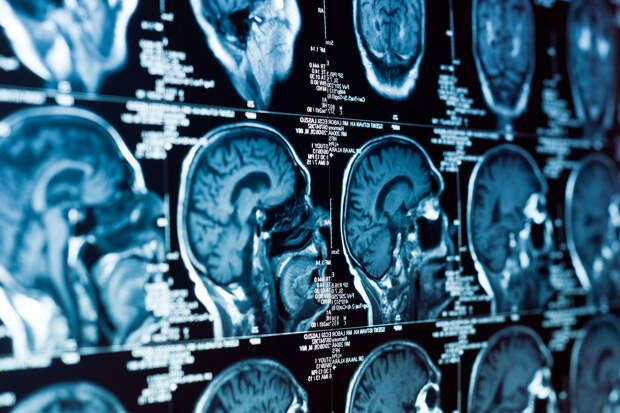

С помощью усовершенствованной микроскопии исследовательница Элейн Беарер обнаружила мельчайшие пластиковые частицы в сосудах и тканях мозга людей, страдавших деменцией. Анализ показал, что эти загрязнители могут вызывать или усиливать повреждения сосудов, провоцируя микроинсульты, кровоизлияния и утолщение артерий.

Беарер предложила новую классификацию сосудистой деменции, выделив несколько типов сосудистых повреждений — от утолщения артерий до микрокровоизлияний и отложений бета-амилоида, характерных также для болезни Альцгеймера. Анализ тканей показал, что во многих случаях эти патологические изменения сопровождались присутствием микропластика в стенках сосудов и белом веществе мозга.

Основной функцией белого вещества выступает координация информации в центральной нервной системе. Благодаря белому веществу мозг способен "общаться" между своими участками.

По мнению ученых, именно микрочастицы пластика могут запускать воспаление, нарушать эластичность сосудов и усугублять процессы, ведущие к нейродегенерации. Исследователи подчеркивают: если эта связь подтвердится, это станет еще одним доказательством того, что загрязнение окружающей среды напрямую влияет на здоровье человека — вплоть до структуры и функций мозга.